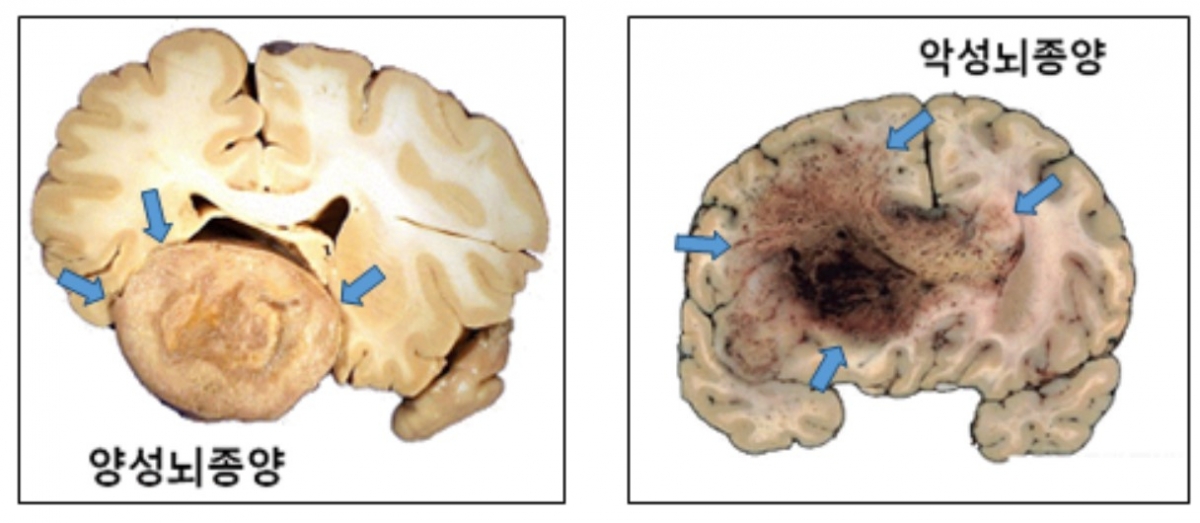

뇌종양은 조직학적 특성에 따라 '양성'과 '악성'으로 나눈다. '양성 뇌종양'은 성장 속도가 1년에 2㎜ 미만으로 느리다. 주변 부위와 비교적 명확히 구분되기 때문에 수술을 통한 완치 가능성도 높다. 종양의 크기·위치에 따라 일상생활이 불편할 수 있어도, 5년 생존율이 90% 이상일 만큼 생명에 거의 지장이 없다. 따라서 별다른 증상이 없는 경우 경과 관찰만 하며, 증상이 있거나 주기적으로 MRI(자기공명영상)를 촬영하며 관찰하다가 성장 속도가 일반적인 경우보다 빠르다고 판단될 때 치료를 고려해도 늦지 않다.

'악성 뇌종양'은 진행이 빠르고, 성장하면서 뇌 조직을 침범하는 경향을 보인다. 뇌교종이 대표적이다. 뇌교종은 뇌신경세포를 지지하는 교세포에서 발생하며, 절반 이상이 악성이다. 양성 뇌교종도 시간이 지나면서 악성화되는 경우가 많다. 뇌교종이 발견되면 일부 예외적인 경우를 제외하고, 대부분 증상이 없더라도 치료가 필수적이다.